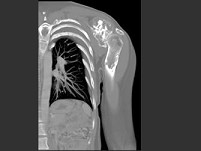

男,27岁,左肩部扪及一硬结1月余,有轻压痛,结合影像学检查,最可能的诊断是()

• A.骨肉瘤

• B.骨软骨瘤

• C.骨巨细胞瘤

• D.尤文肉瘤

• E.骨囊肿